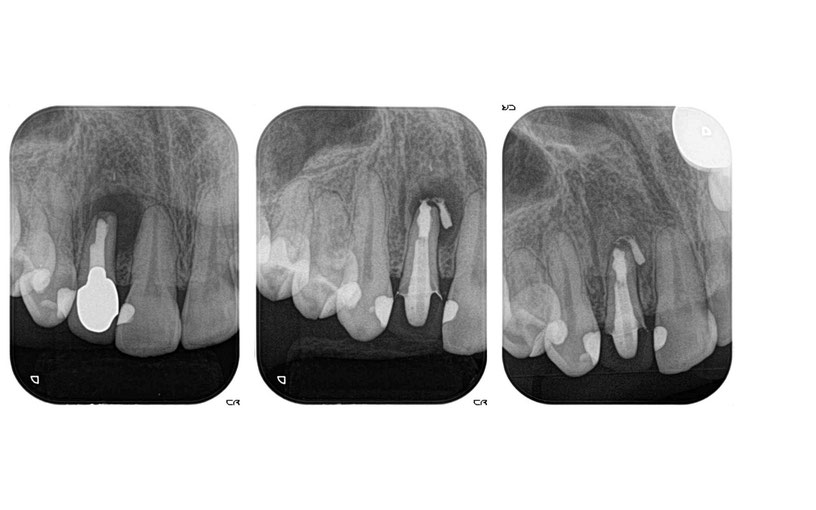

歯の根っこの先に炎症があるため歯を抜くと言われた方の根っこの再治療例です.左側が最初の状態です.根っこの先に骨が吸収して黒い丸い像が見えますが,根っこの中を消毒する事で根っこの先の黒い丸が右側の写真では無くなっています.炎症が無くなっていますので歯を抜かずにそのまま残す事ができました.

歯の根っこが炎症を起こして根っこの先の骨が吸収してしまっている場合、抜いてインプラント治療を勧められる事があります.

歯を抜かずに根っこの神経の治療を行う事で、歯を保存する事が出来る場合があります.

神経を抜いた歯の根っこの先に炎症が起こる場合があります。神経を抜いた歯に差し歯などが入っている場合は、金属の土台を取く必要があるため、金属を取り除くと歯が割れてしまうから歯を抜きましょうと歯医者さんに言われることがあります。

歯を抜かずに根っこの神経の治療を行う事で、歯を保存する事が出来る場合があります.